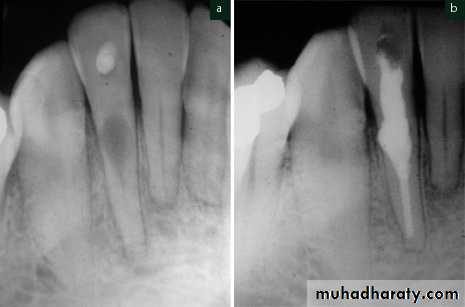

• 5) Radicular cyst

The radicular cyst is an inflammatory cyst which results because of extension of infection from pulp into the surrounding periapical tissues.Etiology

Radiographic Features

Radiographically radicular cyst appears as round, pear or ovoid shaped radiolucency, outlined by a narrow radiopaque marginTreatment